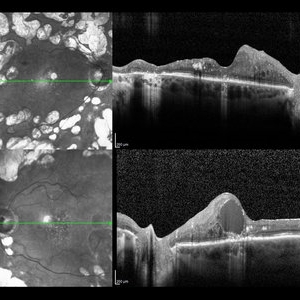

Diabetic Macular Edema

Optical coherence tomography of an 54-year-old female with diabetic macular edema affecting both eyes. Patient has a history of proliferative diabetic retinopathy s/p PRP/PPV/MP/EL, and glaucoma s/p tube shunt in both eyes. There has been a persistence of her macular edema and limited response to antiVEGF therapy, which puts into question whether there is another cause for her edema. Leading the possible causes is her renal insufficiency and fluid retention. Patient was seeing 20/50 in the right eye and 20/80 in the left eye.

Photographer: Olivia Rainey

Imaging device: Heidelberg Spectralis

Condition/keywords: anti-VEGF, diabetic macular edema, edema, glaucoma, optical coherence tomography (OCT), pan-retinal photocoagulation (PRP), proliferative diabetic retinopathy (PDR)